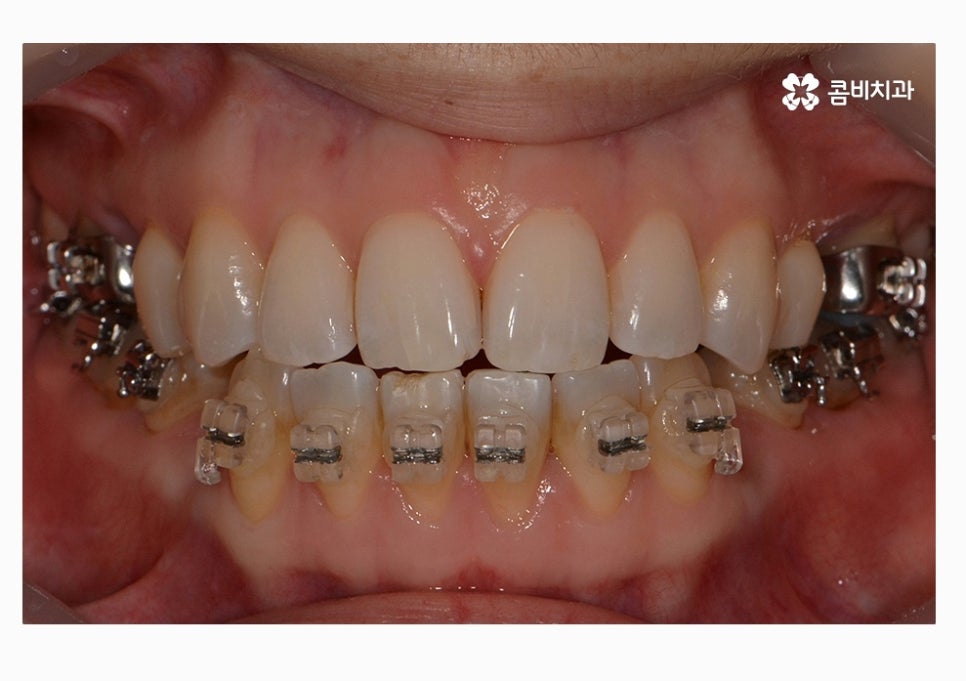

콤비교정은 윗니는 치아의 안쪽에 교정기를 부착하고

아랫니는 치아의 바깥쪽에 장치를 부착하는 방법으로

크게 웃지 않는다면 평소에는 잘 티가 안 나는

심미적으로 우수한 교정 방법이라고 할 수 있어요.

위 환자분의 경우에는 콤비교정의 치료 경과를 보면

아랫니가 정상교합이 되었고 치열도 보다 가지런하게

변화되고 있음을 알 수 있는데요.

콤비교정을 선택하시는 분들 중에서는 이처럼 치열과 함께

부정교합을 개선하고자 하시면서 직업적인 이유 등으로

교정 장치가 잘 보이지 않길 원하시는 분들에게 선호되고 있어요.

위 케이스는 총 1년 9개월 정도의 치료 기간이 소요되었으며,

개개인마다 치료 결과와 기간은 차이가 있을 수 있습니다.